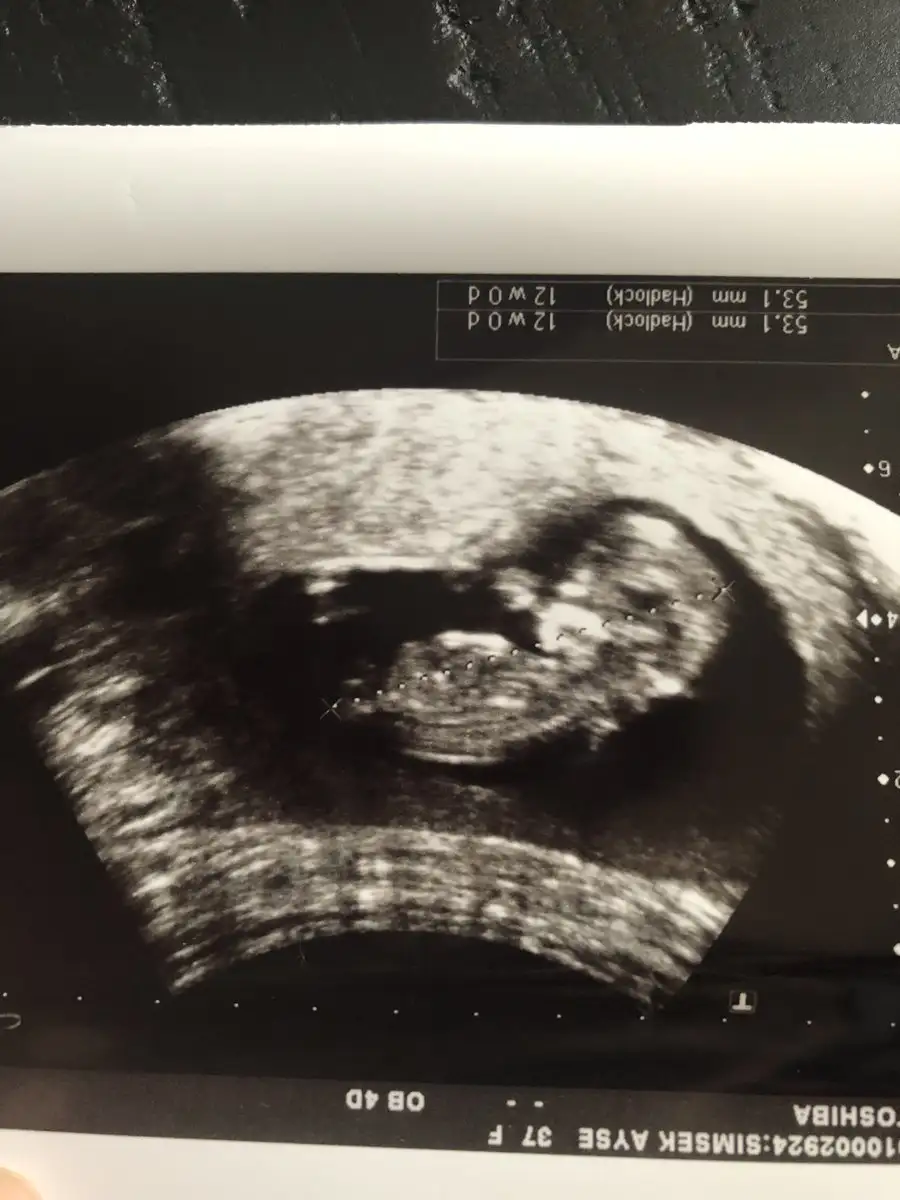

Ohh maşallah harika benim de hep ilerde gidiyo doktorum şimdilik bişey demedi bende sorun yoktur diye düşünüyorum herşeye endişelenir oldum@SLVESTER Merhaba! Canım ilk usg benden gelsin yorum alabilirmiyim. Bugün kontrol vardı ense burun vs. Herşey yolunda ama cinsiyet için erken dedi dr. Bide tam 12 haftalık çıktı normalde 11+3 olması gerekiyordu

Tşkler canım. Sağlıklı olsunlarda gerisi önemli değil şimdi de tarih değişti ağustos annesi oldum bende çok endişeli biriyim zor geldi bu ikincisi ama bugün gerçekten rahatladım onu böyle görünce çok güzeldi sağlıkla kucaklıyalım inşallahOhh maşallah harika benim de hep ilerde gidiyo doktorum şimdilik bişey demedi bende sorun yoktur diye düşünüyorum herşeye endişelenir oldum

Tşkler canım. Sağlıklı olsunlarda gerisi önemli değil şimdi de tarih değişti ağustos annesi oldum bende çok endişeli biriyim zor geldi bu ikincisi ama bugün gerçekten rahatladım onu böyle görünce çok güzeldi sağlıkla kucaklıyalım inşallah